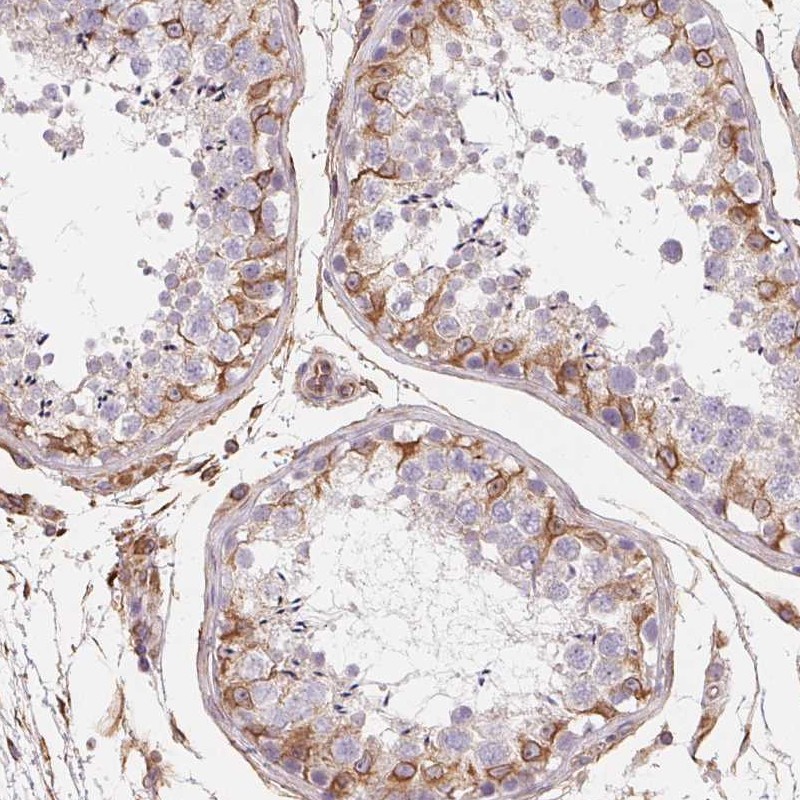

Immunohistochemical staining of human testis shows strong cytoplasmic positivity in subset of cells in seminiferus ducts of testis.